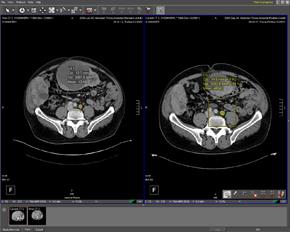

October 7, 2009 - Computed tomography (CT) is the modality of choice in the evaluation of blunt renal injury, according to a study published in the September 2009 issue of Radiolographics.